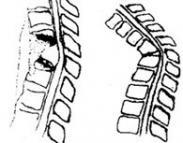

胸、腰椎椎体单纯性、楔形压缩骨折

628健康网为您分享有关胸、腰椎椎体单纯性、楔形压缩骨折的症状,胸、腰椎椎体单纯性、楔形压缩骨折的治疗方法,胸、腰椎...

椎体严重楔形变并伴小关节半脱位

628健康网为您分享有关椎体严重楔形变并伴小关节半脱位的症状,椎体严重楔形变并伴小关节半脱位的治疗方法,椎体严重楔形...